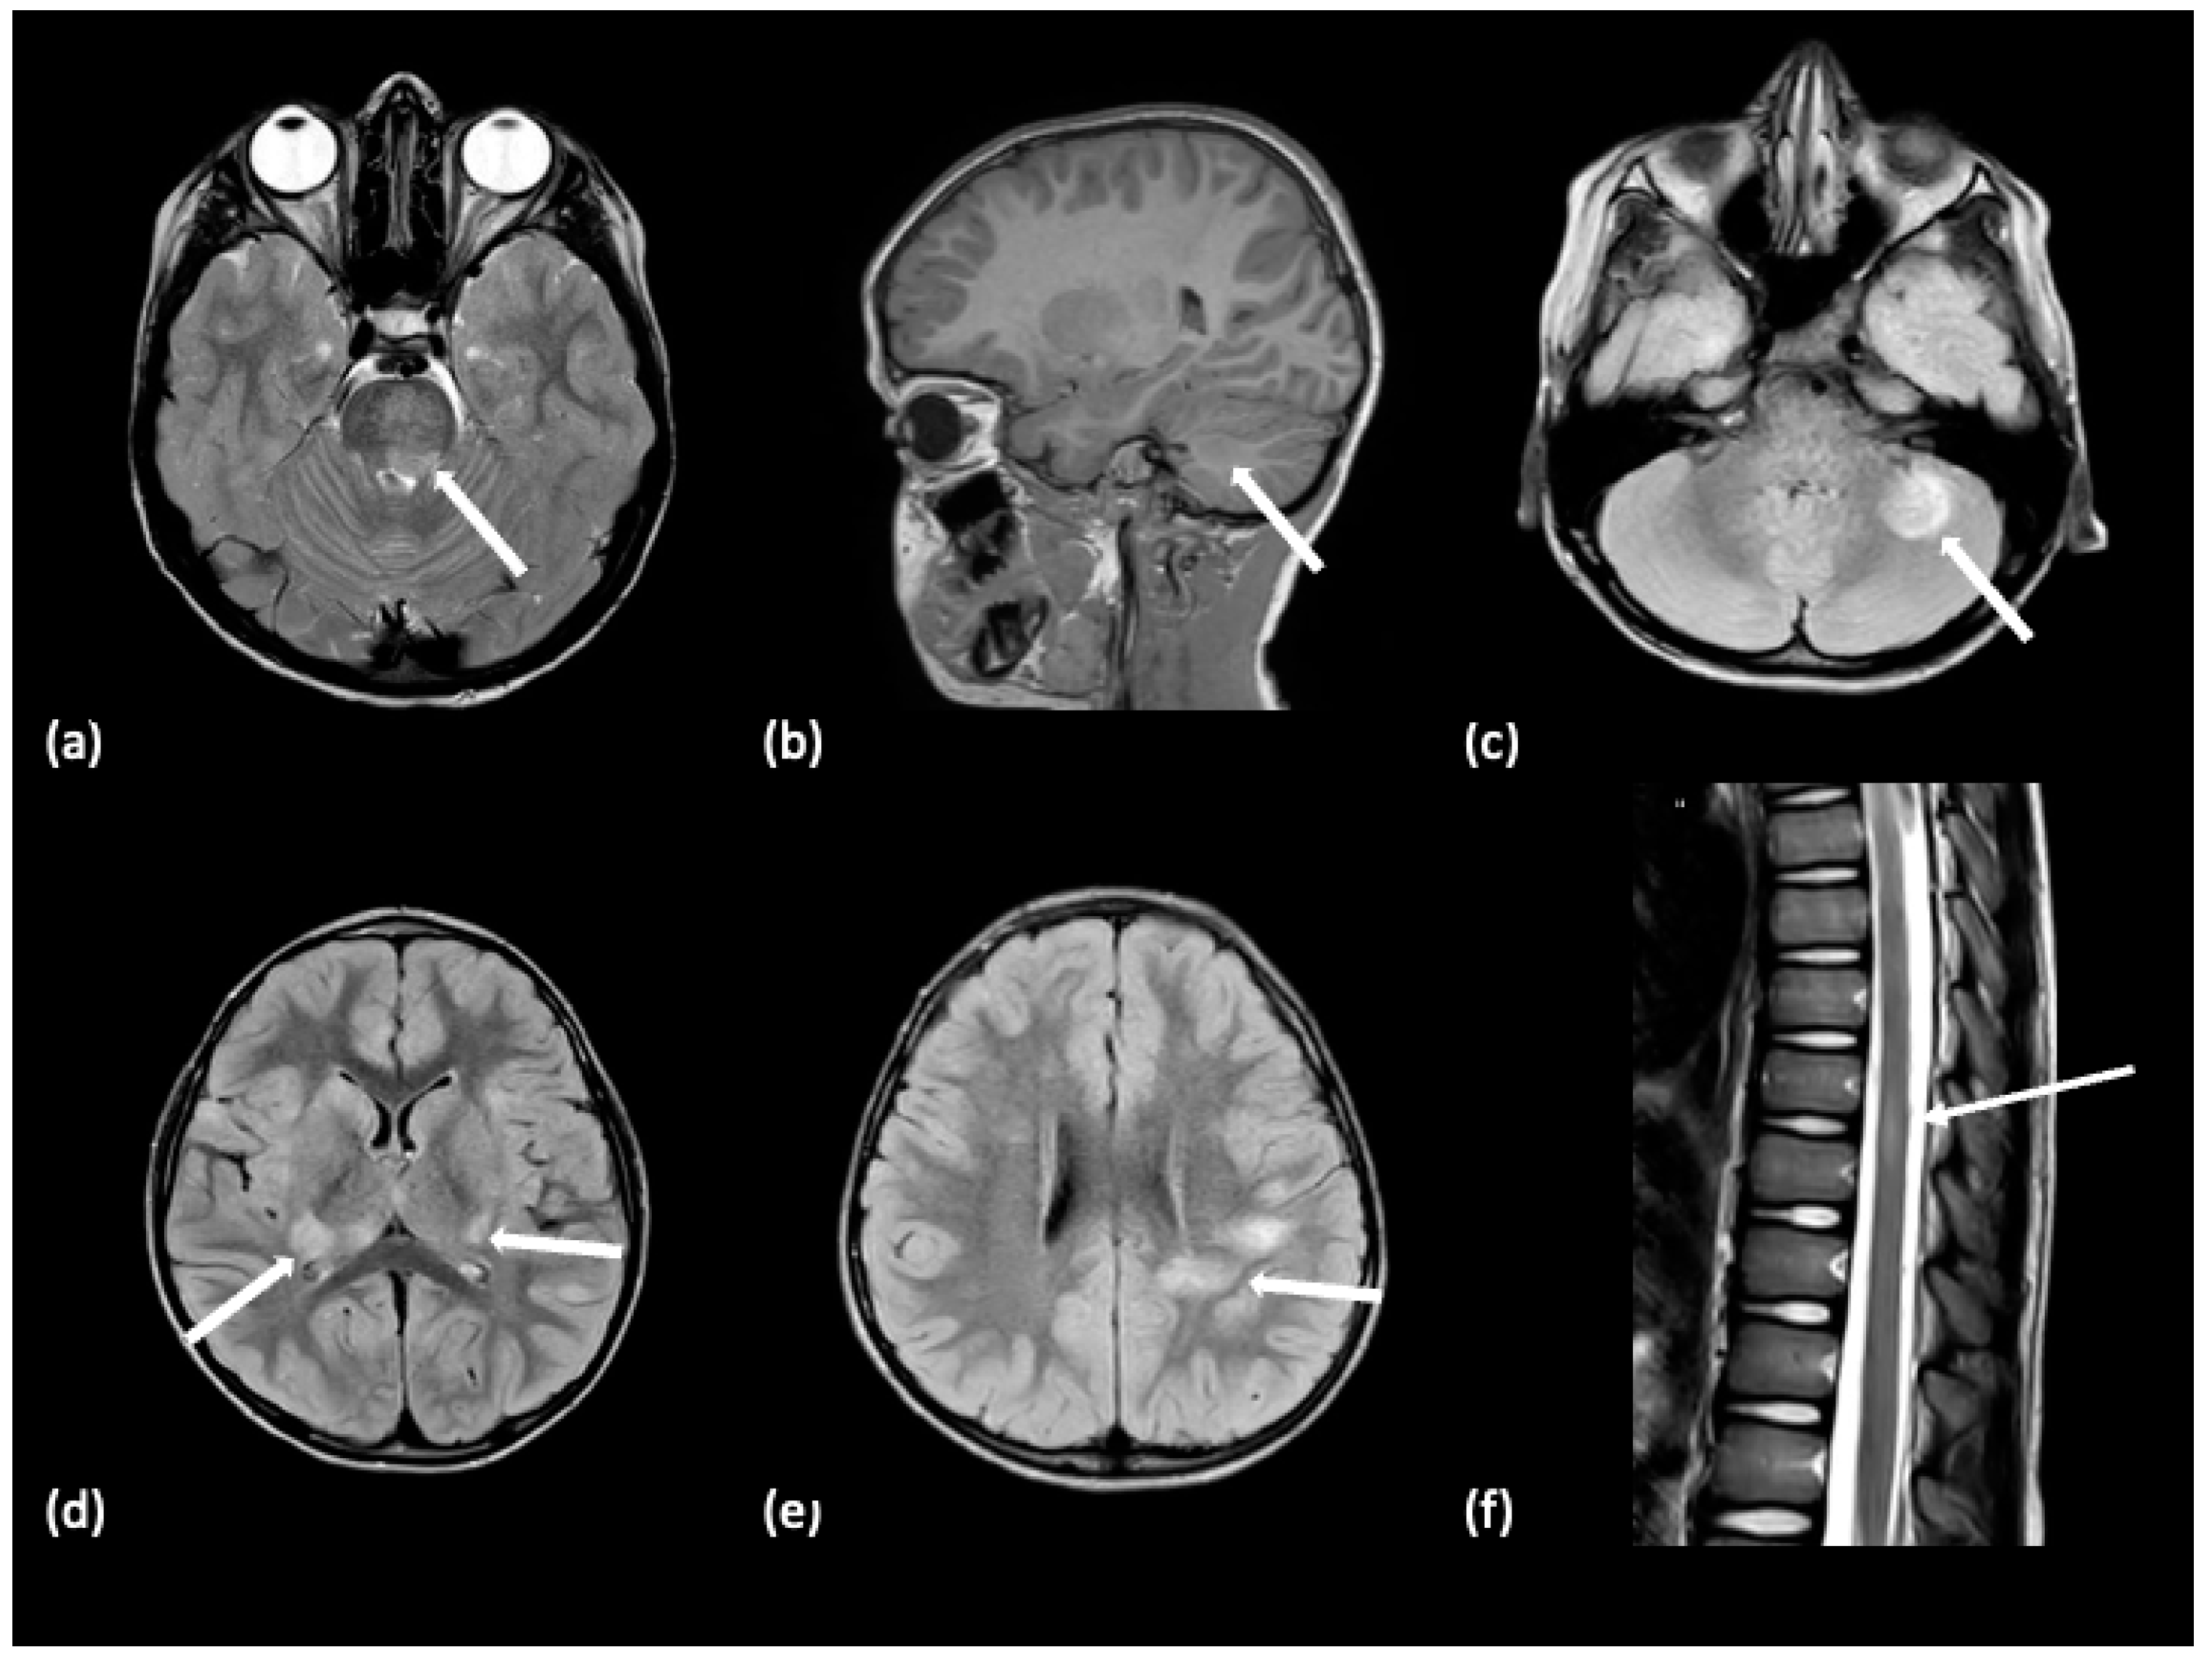

| NMOSD | At presentation: >60% unremarkable | N/A | N/A | N/A |

| At presentation: <40% with findings | Corpus callosum, subcortical white matter, periventricular white matter, area postrema, brainstem, near the 3rd and 4th ventricles, thalamus and hypothalamus; Spinal cord transverse myelitis | Cloud-like pattern; Linear, pencil-thin of the ependymal surface of lateral ventricles | Corpus callosum lesions-large, irregularly shaped; Tumefactive, confluent lesions->3 cm | |

| NMOSD with ON | At presentation: <40% with findings | Bilateral, longitudinally extensive posterior optic nerves (optic chiasm, optic tracts); spinal cord—central over three or more vertebral segments | Infraorbital fat enhancement | Initial presentation with ON; relapses with transverse myelitis |